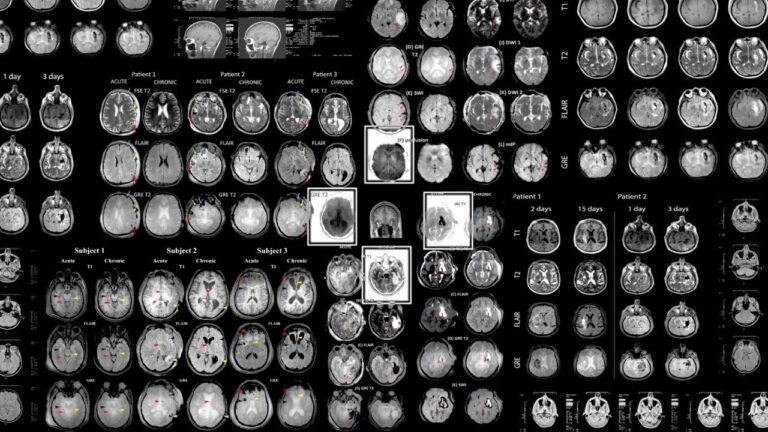

Early Detection in Alzheimer’s

The key to treating and managing many brain diseases is to catch them early, before symptoms even appear. For researchers like Paul Thompson at the USC Mark and Mary Stevens Neuroimaging and Informatics Institute, they believed they could discover hidden factors of diseases using machine learning technology. Calling in the help of USC computer science research assistant professor Greg Ver Steeg, researchers studied how using machine learning to identify potential blood-based markers of Alzheimer’s disease.